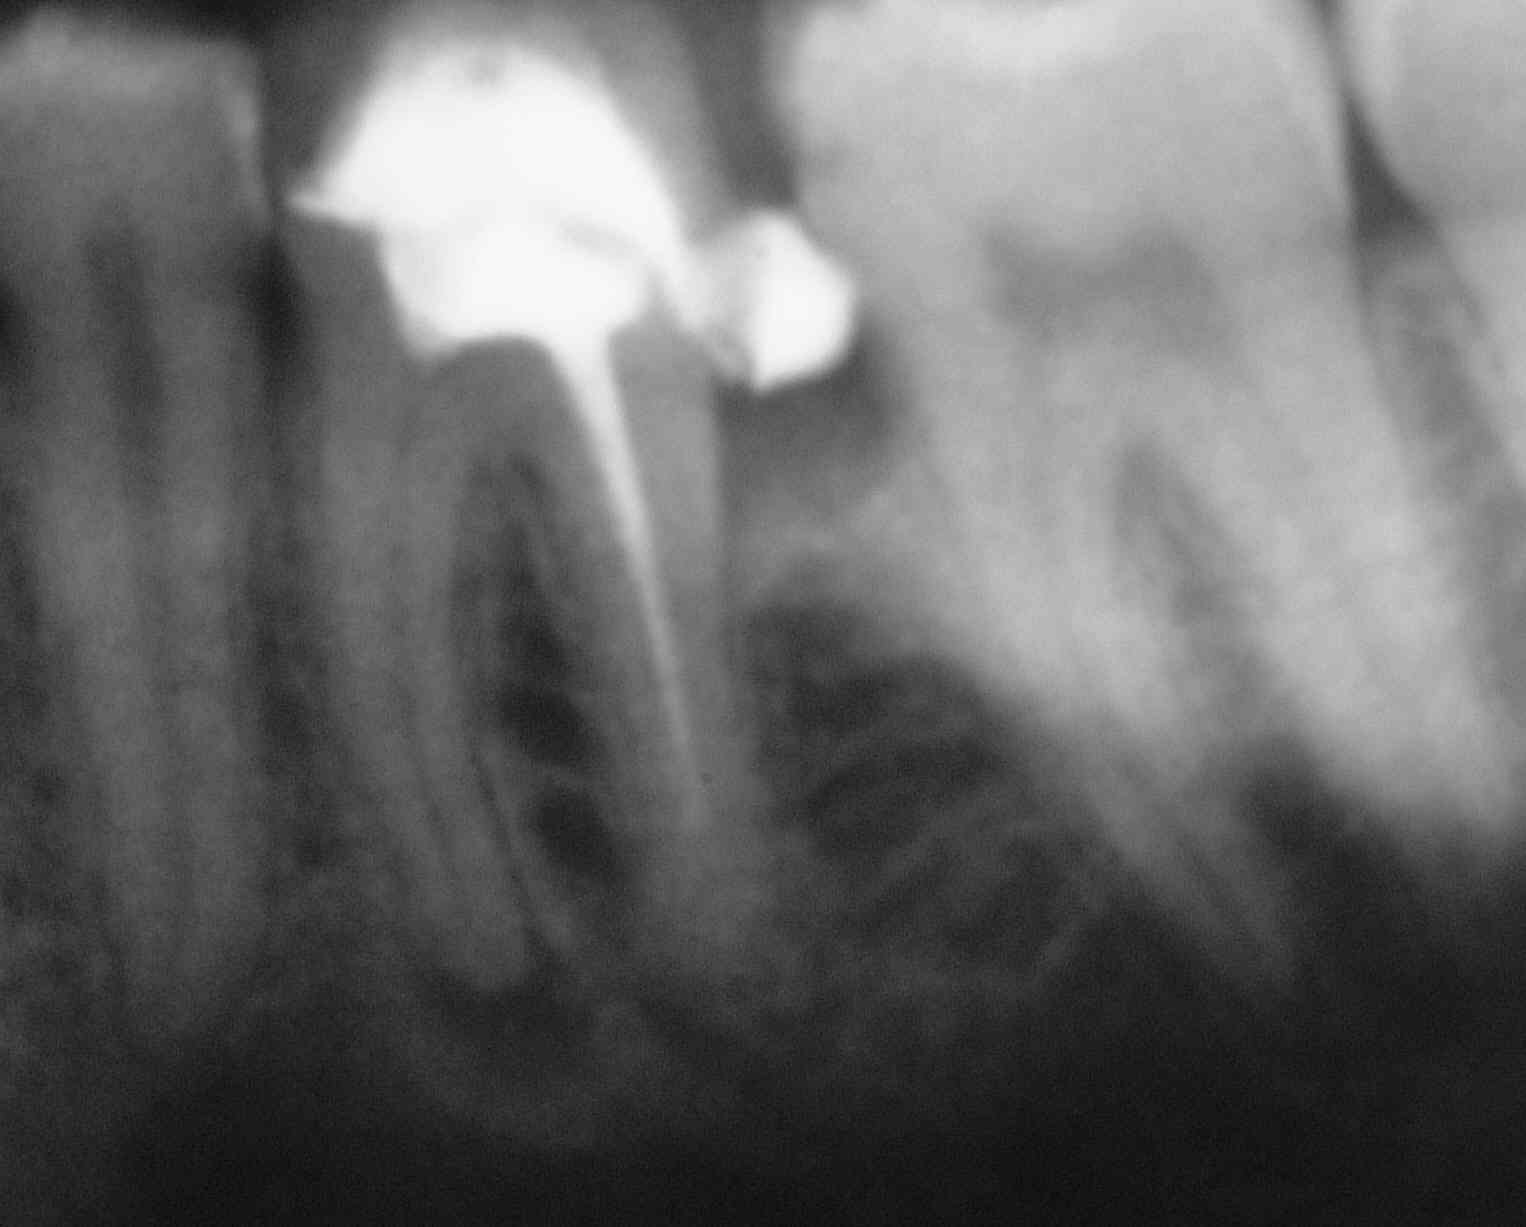

Nach der wissenschaftlichen Literatur kann man unter Anwendung des Endodontie-Protokolls nach dem sogenannten Goldstandard bei devitalen Zähnen mit apikaler Ostitis eine klinische und röntgenologische Ausheilungsquote von gerade einmal um 70% erreichen. Bei der Revision von Zähnen mit apikalen Aufhellung sinkt diese Quote trotz „intelligenter Fallauswahl“ (intelligent case selection) noch einmal deutlich auf 60%ab.

Auf der Basis einer sorgfältigen Evaluation unserer Fälle können wir ganz im Gegensatz dazu aussagen, dass wir in diesen Fällen mit unserem Endodontie-Protokoll eine Quote röntgenologisch knochendichter Ausheilung von sehr nahe an 100% erreichen. Dies gilt auch für bereits wurzelspitzenresezierte Zähne, die exazerbieren und keine Längsfraktur aufweisen.

Und zum Abschluss noch eine schöne Doublette:

Galerie: